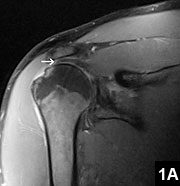

Rotator Cuff Tear MRI | New Health Advisor

Figure 1: Rotator Cuff Tear This rotator cuff tear is seen in the The muscle is lit up in bright white and you can see a dark spot indicating the Figure 2: Partial Rupture This is a partial rupture of one of the rotator cuff The red arrow indicates the rupture Figure 3: Complete Rotator Cuff Tear